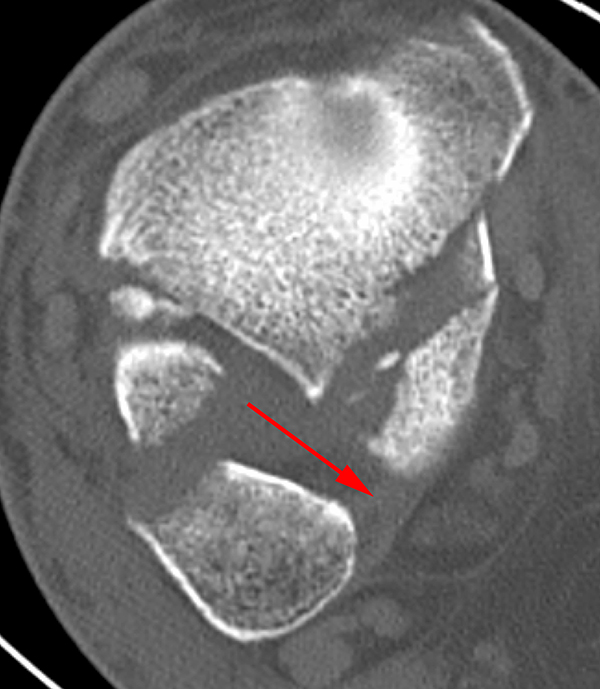

Liegt eine Fraktur des oberen Sprunggelenks vor, ist sowohl zur Entscheidung für ein konservatives oder operatives Vorgehen, als auch zur Operationsplanung, ein ausreichendes Verständnis der Fraktur und ihrer Morphologie notwendig. Insbesondere bei komplexen Verletzungen ist dafür die konventionelle Röntgenaufnahme in vielen Fällen nicht ausreichend. So konnten z.B. Black et al. zeigen, dass die operative Strategie zur Versorgung von OSG-Frakturen in 24% basierend auf einer zusätzlichen CT-Bildgebung relevant geändert wurden 7. Dies betraf die Lagerung, die Wahl des Zuganges und die Art der osteosynthetischen Versorgung. Besonders häufig änderte sich das Vorgehen bei Verletzungen des medialen (21%) und des posterioren Malleolus (15%). Darüber hinaus führten dislozierte (dislozierte Frakturen 31% vs. nicht-dislozierte Frakturen 20%) oder komplexe Frakturen (Trimalleolar-Frakturen 29% vs. Unimalleolar-Frakturen 10%) besonders häufig zu relevanten Änderungen des operativen Vorgehens. Die Computertomographie ist daher, insbesondere bei Bi- und Trimalleolar-Frakturen, essentiell für das Verständnis der Fraktur und somit für die Planung und Durchführung der Operation. In Abbildung 4 und 5 sind exemplarisch ein Röntgen- und ein CT Befund gegenübergestellt.

Seit einer Untersuchung von Nelson und Jensen aus dem Jahre 1940 wird allgemein akzeptiert, dass die Indikation zur Osteosynthese des Tibiahinterkantenfragments nur dann besteht, wenn die Größe mehr als ein Drittel (nach zahlreichen Autoren auch ein Viertel) der Gelenkfläche beträgt (Abbildung 15) 25. Dieses bis heute allgemeinakzeptierte Vorgehen basiert auf der Beobachtung von lediglich acht unterschiedlich versorgten Patienten. Seither gibt es keine weiteren klinischen Studien, die dieses Vorgehen stützen. Mittlerweile gibt es allerdings zunehmend Hinweise, dass bei der Versorgung des posterioren Malleolus viele andere Faktoren eine wichtige Rolle spielen 26. Da an der Tibiahinterkante das Lig. tibiofibulare posterius ansetzt (Abbildung 16), wird durch die offene Reposition und Stabilisierung die Integrität und die physiologische Spannung der hinteren Syndesmose rekonstruiert (Abbildung 17). Dies ist entscheidend für die anatomische Reposition der Fibula in der Tibiainzisur.